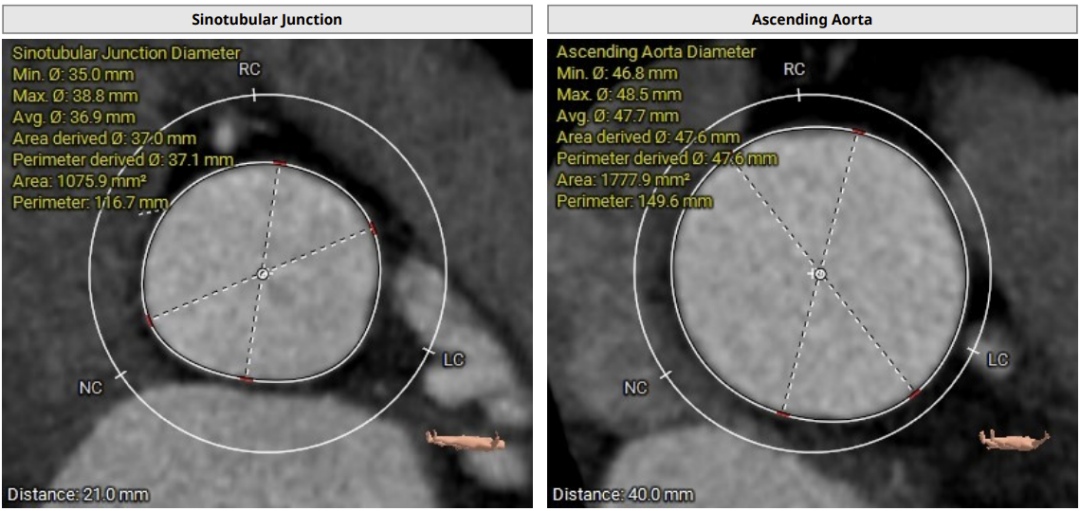

术前CT评估:

CT分析提示:TypeI型二叶瓣,左右瓣叶融合,瓣叶增厚,重度偏心性钙化,钙化位于无冠瓣叶及右无瓣叶交界处,且钙化延伸至LVOT2.5mm,舒张期可见瓣叶关闭不全间隙,右冠高度可,左冠开口平面可见瓣叶,左冠堵塞风险极高,心室略大,室壁厚度可,非横位心,升主动脉瘤样扩张,大血管走行自然,右侧髂总动脉血管细小。

瓣环直径29mm,LVOT直径31.1mm,typeI型瓣叶且偏心钙化位于无冠窦,按照常规瓣膜型号选择标准,但考虑患者两叶瓣,且左冠状动脉阻塞风险极高,downsize选择瓣膜型号,拟植入26mmVenus-A,备29mmVenus-A,高位释放,采用可回收输送系统,术中22mm球囊预扩张sizing后确定最终瓣膜型号选择。左冠预置支架保护。以左侧股动脉为主入路。